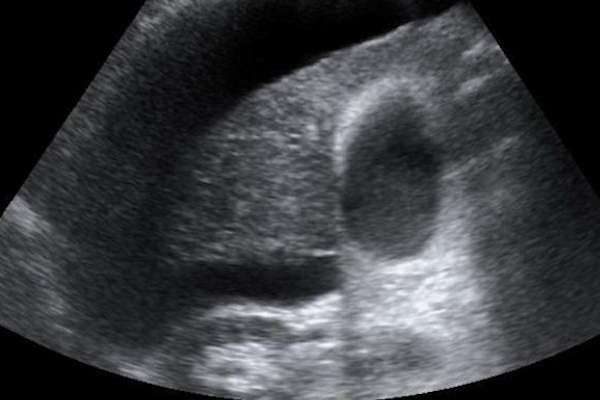

当肝脏受伤它形成疤痕,“当你把它以同样的方式你的皮肤呢,”艾拉·雅各布森,医学博士,在纽约大学朗格尼医学中心医学和肝病主任教授说。在某些情况下,疤痕组织可以建立为改变机关的质感广泛的网络,给它一个“块状,颠簸”的出现,据雅各布森博士。肝损伤的晚期阶段被称为肝硬化,这意味着血液无法再正常流过你的肝脏。

一个肝病患者的困难是,症状往往不裁剪,直到晚期。如果你做的事通知,最常见的症状包括疲劳,恶心,体重减轻,易出血或瘀伤,黄疸和肿腿。幸运的是,一些血液和影像学检查可用于诊断疾病。一个是所谓的弹性,后者衡量的弹性(或僵硬),你的肝脏组织可能会通过你的身体传递声波。因为疤痕组织变硬的肝脏,这给扫描医生的破坏程度的快照。

当人们有肝硬化,他们更容易患上一种称为肝癌肝癌。研究人员并不完全了解这两种疾病之间的联系,但有一种解释是,疤痕组织和持续的炎症的积累造成,其中癌症肿瘤更容易生长的环境。不管究竟为什么肝脏上的疤痕是与癌症“肝硬化的人应定期进行肝癌筛查,”雅各布森博士说。